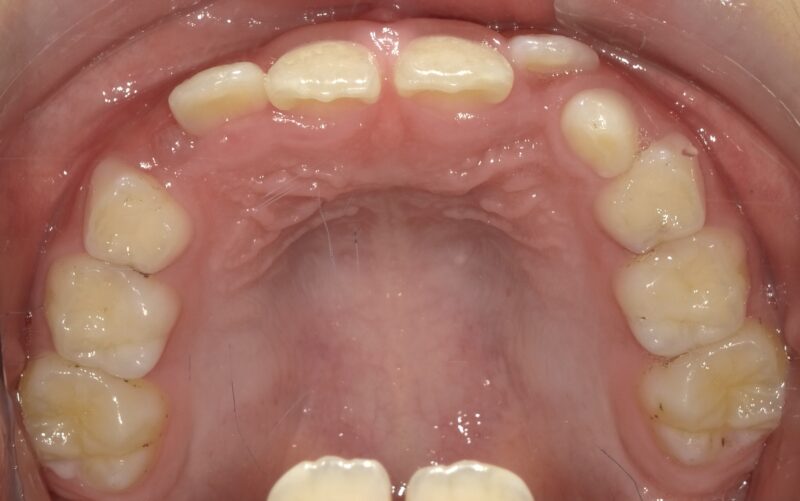

【症例】混合歯列期の反対咬合(8歳・男児)

混合歯列期に上顎の発達不足が見られ、反対咬合を呈していたため、治療介入。

上顎の成長を促すことで、骨格性の反対咬合への進行を防ぐことができました。

■ 初診時の状態

この時期はすでに上下の1番・2番・6番が萌出しており、

顎の成長コントロールが可能な重要なタイミングでした。

反対咬合を放置すると、

・ 上顎の成長が抑制される

・ 下顎が前方に成長しやすくなる

・ 将来的に骨格性の受け口へ進行する可能性

があるため、早期の1期治療を開始しました。